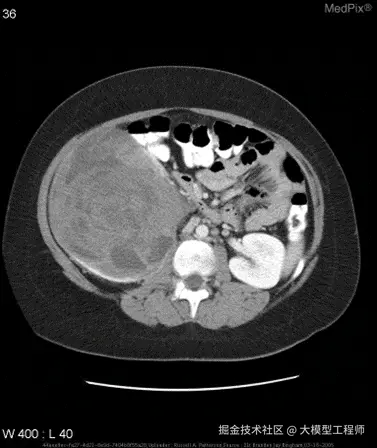

示例:针对如下影像,微调前后的输出

微调前:

{

"query": "is the liver visible in the image?",

"true": "no",

"infer": "yes, the liver is visible in the image. it appears as a large, dark gray structure located in the upper left quadrant of the abdomen.",

"exact_score": 0,

"cosine_score": 0.3227266048281184

}

微调后:

"infer": "no",

"exact_score": 1,

"cosine_score": 1.0